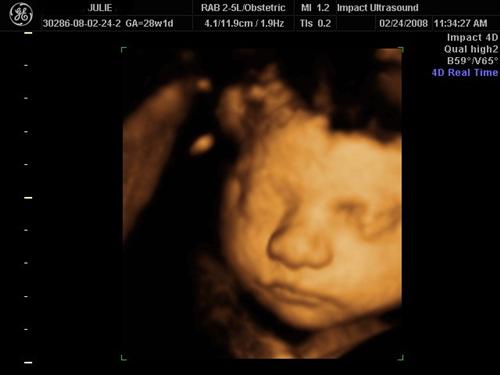

3D SONO PICS

Here is my He looks just like his daddy!

Awww, he is smiling in the first one! Glad you had a great experience. The pictures are great!!!

The first one (smiling) is my favorite. Now I am going to try to upload my DVD to photobucket... I hope I can get it to work!